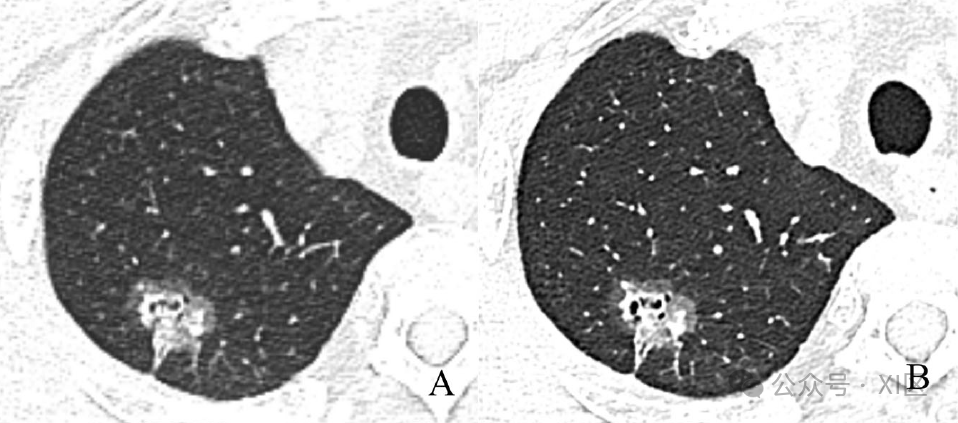

EID与PCD CT图像质量的比较。57岁男性,右上肺轴位CT图像显示亚实性结节,病理证实为浸润性肺腺癌。PCD CT表现清晰,EID CT表现模糊。与1.0 mm EID CT图像(A)相比,1.0 mm PCD CT图像(B)的主观图像质量被评为“极好”;辐射剂量PCD减少了18%。